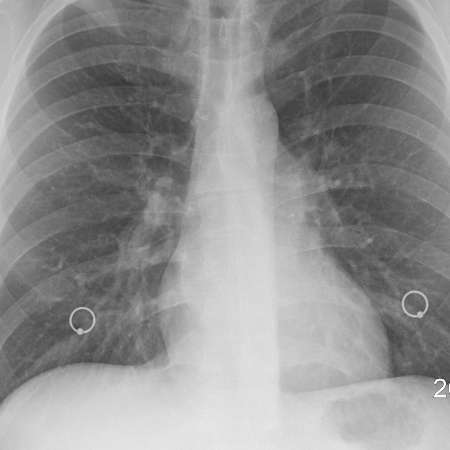

폐섬유증

폐섬유증은 폐 쪽의 조직이 섬유화 되어 흡기와 폐활량을 제한하는 상태를 나타냅니다. 이는 폐의 기능을 점차 손상시키고, 호흡 곤란, 기침, 가슴 통증 등의 증상을 유발할 수 있습니다. 주로 폐조직에 염증이나 손상이 발생하면서 섬유화 과정이 진행되며, 이로 인해 정상적인 폐조직 대신 섬유 조직이 증가하게 됩니다.